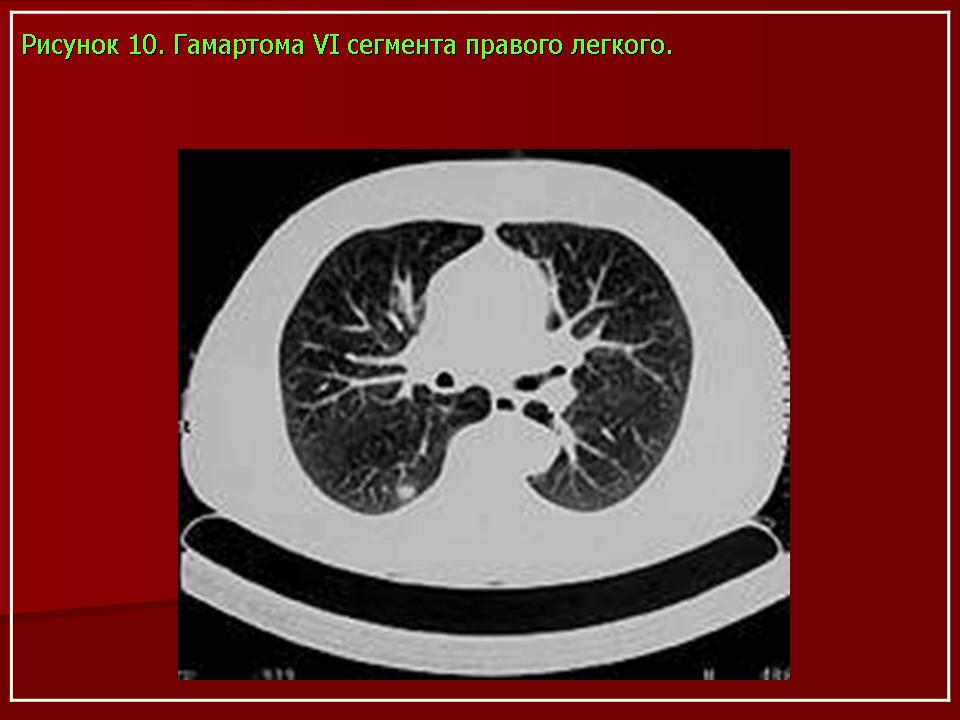

Практически все круглые опухоли в той или иной степени вызывают диагностические затруднения. Периферический рак легкого приходится дифференцировать с рядом заболеваний:

• Новообразования: злокачественные — бронхоальвеолярный рак (рис. 8), саркома, метастазы (рис. 9);

доброкачественные (рис. 10, 11).